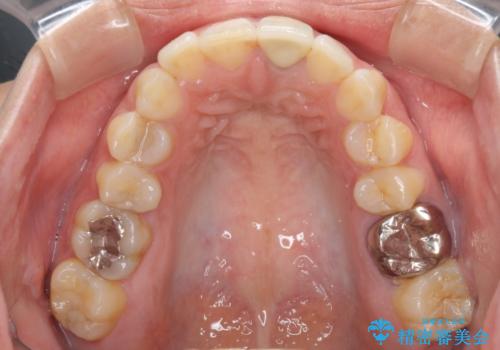

- 前歯をメタルの被せものにしており、セラミックに変えるのを希望された患者様です。

土台も金属だったため、歯がかなり黒く変色していました。

色は完全にとるのが不可能であることをご了承頂いた上で、土台と被せものの治療を行いました。

今回は歯自体が黒くなって歯茎から透けて見えている黒ずみのため、セラミック治療で改善させることは困難だというお話をしました。その上でできる範囲できれいに治療することになりました。

今回のように歯自体が金属イオンで黒く変色すると、被せものをメタルフリーにしても黒ずみをすべて隠すのは困難になります。一方、被せものの金属が見えていることが原因の黒ずみの場合は、セラミック治療できれいになりますので、気になる方は一度ご来院ください。